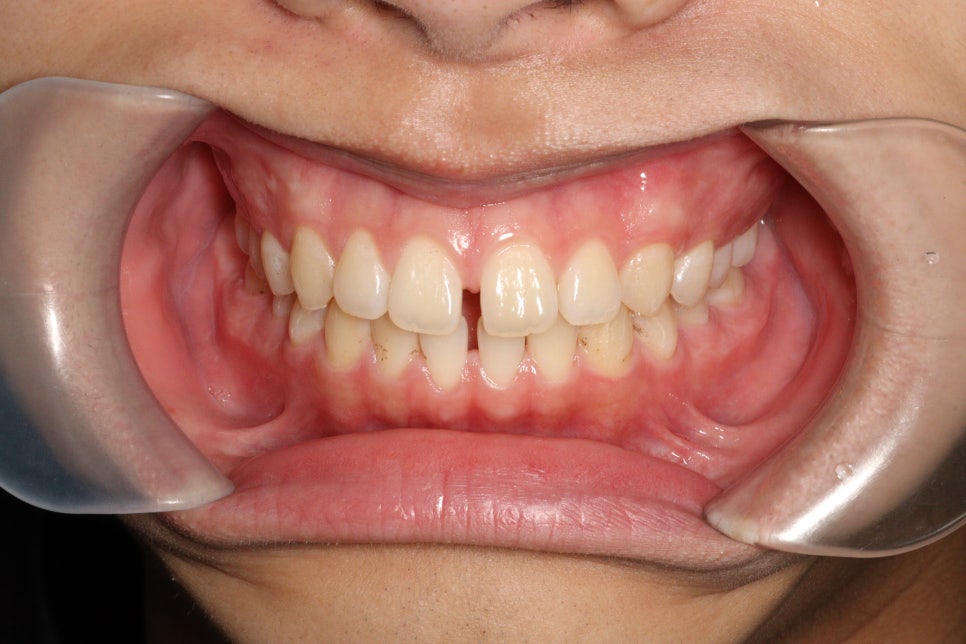

재제작을 통해 제 마음에 안들던 교합까지 형성해드리고, 치아배열도 마무리.

공간도 모두 없어지고 배열도 좋아졌습니다

간단한 교정치료이긴 하지만 제 욕심도 채우고 만족할만한 결과를 얻게 된 환자분의 후기입니다.

이 케이스의 경우 약 4개월 정도 기본 치료가 진행되었고, 재제작을 통해 총 약 9개월간 치료가 진행되었습니다. 치료 기간은 개인의 치아 상태와 치료 계획에 따라 달라집니다.

벌어진 앞니는 인비절라인의 가장 기초적인 치료 중 하나로, 치료 결과가 매우 좋은 편입니다. 이 케이스에서도 공간이 모두 닫히고 치아 배열이 개선되었습니다.

인비절라인 재제작은 초기 치료 계획대로 진행한 후 추가적인 개선이 필요할 때 시행됩니다. 이 케이스에서는 교합 개선과 치아 배열 마무리를 위해 재제작을 진행했습니다.